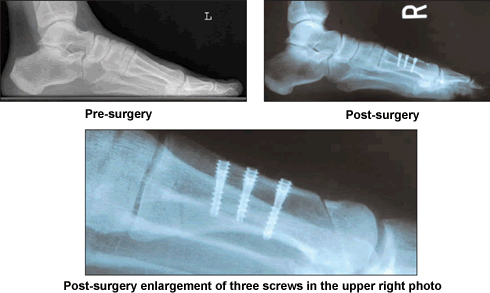

My daughter had moved to San Francisco, but my pain became unbearable. In August of 2004, I searched for information about my problem on The Baptist's web site. There I found Dr. Leavitt's credentials and read his articles on foot reconstruction. I telephoned The Baptist and asked to speak to Dr. Ken Leavitt. At his request, I had x-rays sent to him, then I talked to him twice more by phone from my home in Santos, Brazil.

I owe Dr. Leavitt so much that sometimes, I look at my feet to make sure all has been real. Thank God. Thank you Dr. Leavitt a million times. My feet now make me happy. They are doing very well. They are the feet I had dreamed of for a lifetime. They still complain when in pointed shoes. It will be for a while, it seems to me. I keep exercising and stretching the tissues. It has been three months now and I am running easily and comfortably along the hot sands of my country.